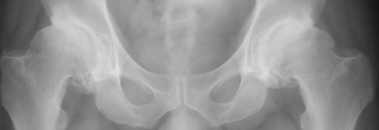

Двусторонний коксартроз 1

Уважаемые коллеги! На консультации пациент, 47 лет. Жалобы на ограничение движений в тазобедренных суставах, возникшие 1,5 года назад.

Около года назад появились боли справа. Лечился консервативно. С незначительным эффектом. Рефмеханик, до последнего времени ходил в море. Анализы - норма. Объективно: утиная походка, ограничение сгибания в тазобедренных суставах до 90 градусов. Ротация отсутствует. Отведение ограничено незначительно.

Хотелось-бы услышать мнения по лечению, в частности - имеют-ли смысл операции не эндопротезирования?